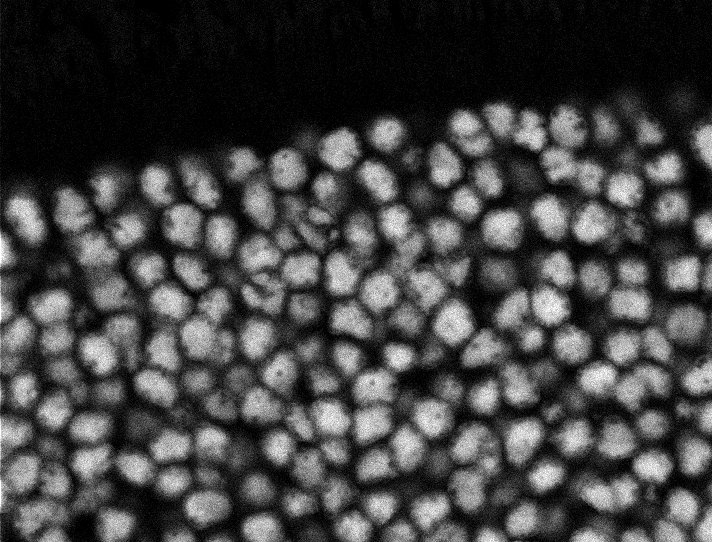

Nuclei